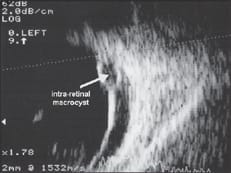

As anticipated, gravity had caused the lens to now be located in the inferior vitreal cavity (see figure 2). Also, we imaged a retinal detachment (see figure 3) and an intraretinal macrocyst (arrow), which indicated that the retinal detachment was long-standing.

Figure 3: Retinal detachment with an intraretinal macrocyst (arrow)